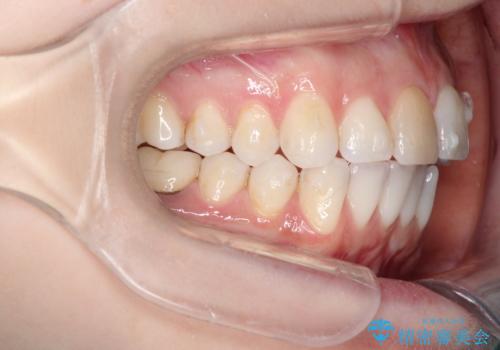

インビザラインによる非抜歯での八重歯の矯正

- 左上の八重歯と、上の歯のがたつきを主訴に来院されました。

上の奥歯を後方に移動させてスペースを作るのと、歯と歯の間をわずかに削り歯を並べる計画としました。

非常に強力的な患者様であったので、上下の正中も合わせ、ガタガタも改善することができました。